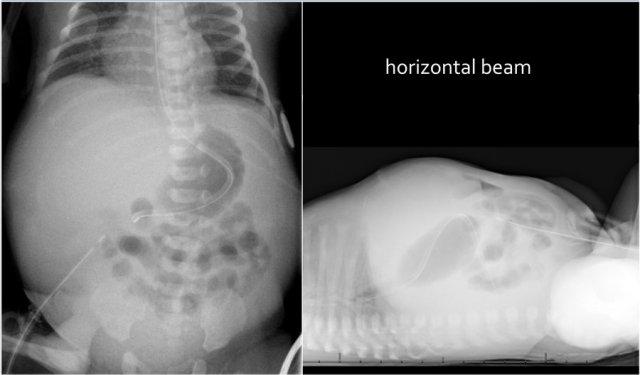

Các hình ảnh cho thấy một trường hợp điển hình của viêm ruột hoại tử với khí trong thành ruột.

Trên hình chụp tia ngang, không có dấu hiệu khí tự do trong ổ bụng.

Đây là hình ảnh của một trẻ sơ sinh phát triển viêm ruột hoại tử.

Ở giai đoạn sớm này, X-quang chỉ cho thấy hình ảnh giãn ruột không đặc hiệu.

Ở giai đoạn này, không thể xác lập chẩn đoán.